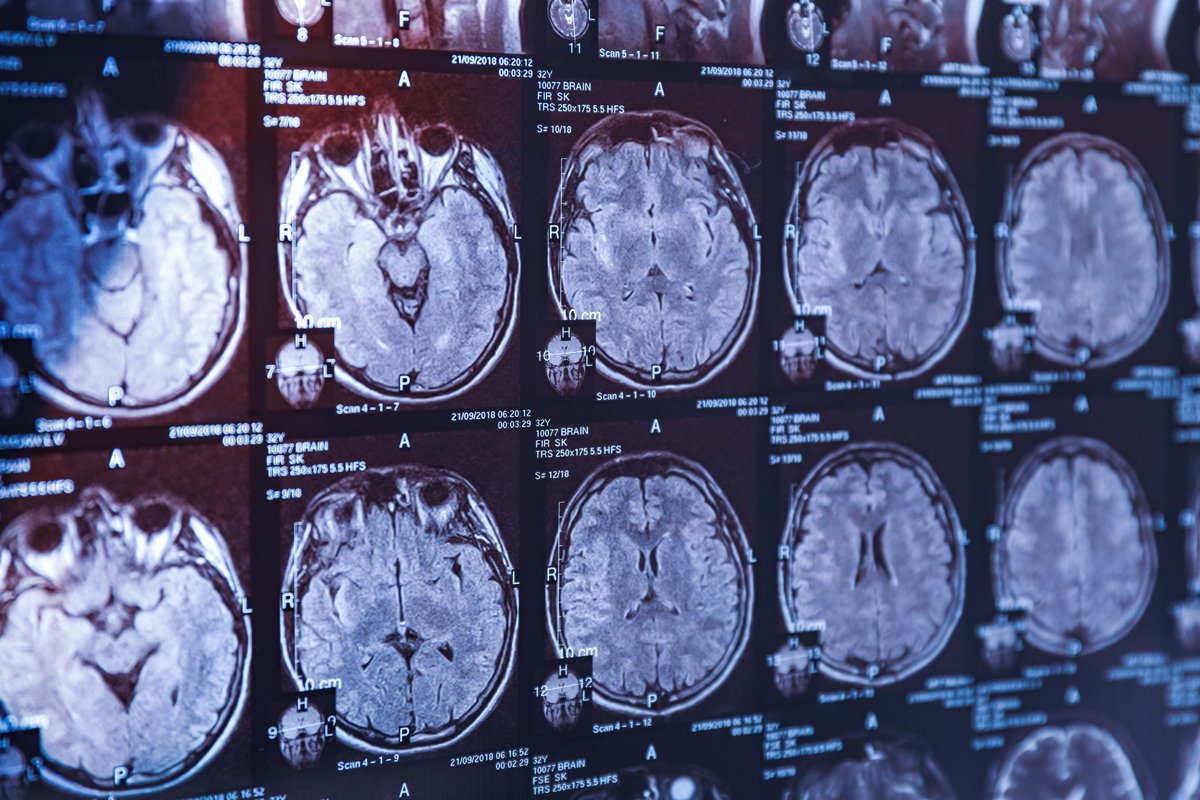

Фото: Pixel-shot / Alamy / Vida Press